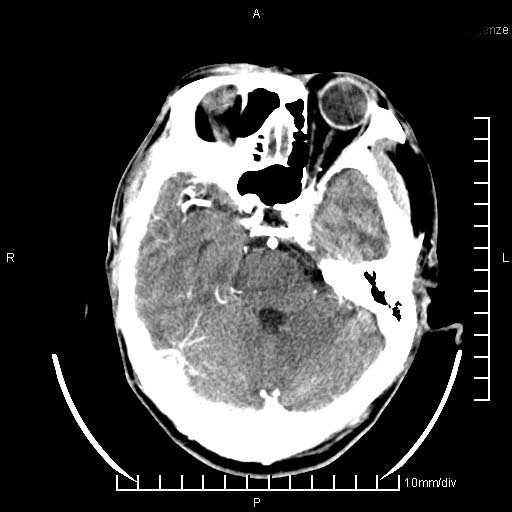

临床以双下肢浮肿,疼痛收治,无明显神经系统症状,既往无梗塞,出血病史。左颞叶见低密度灶,考虑什么?

考虑左侧颞叶脑软化灶。

无强化 无占位 软化灶吧

无强化、 无占位、局部脑沟增宽, 软化灶吧。